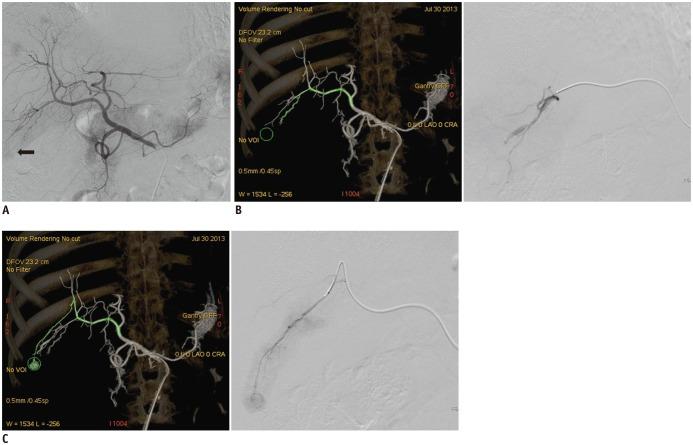

The study included 50 patients with 80 HCC nodules who received transarterial chemoembolization. Standard digital subtracted angiography (DSA) and CBCTA were systematically performed and analyzed. Three settings of the FPFL software for vascular tree segmentation were tested for each tumor: the default, Group D; adjusting the proportion of segmented tumor area between 30 to 50%, Group L; and between 50 to 80%, Group H.

In total, 109 feeder vessels supplying 80 HCC nodules were identified. The negative predictive value of DSA, FPFL in groups D, L, and H was 56.8%, 87.7%, 94.2%, 98.5%, respectively. The accuracy of DSA, FPFL in groups D, L, and H was 62.6%, 86.8%, 93.4%, 95.6%, respectively. The sensitivity, negative predictive value (NPV), and accuracy of FPFL were higher in Group H than in Group D (p = 0.041, 0.034, 0.005). All three segmentation sensitivity groups showed higher specificity, positive predictive value, NPV, and accuracy of FPFL, as compared to DSA.

FlightPlan for Liver is a valuable tool for increasing detection of HCC tumor feeding vessels, as compared to standard DSA analysis, particularly in small HCC. Manual adjustment of segmentation sensitivity improves the accuracy of FPFL.